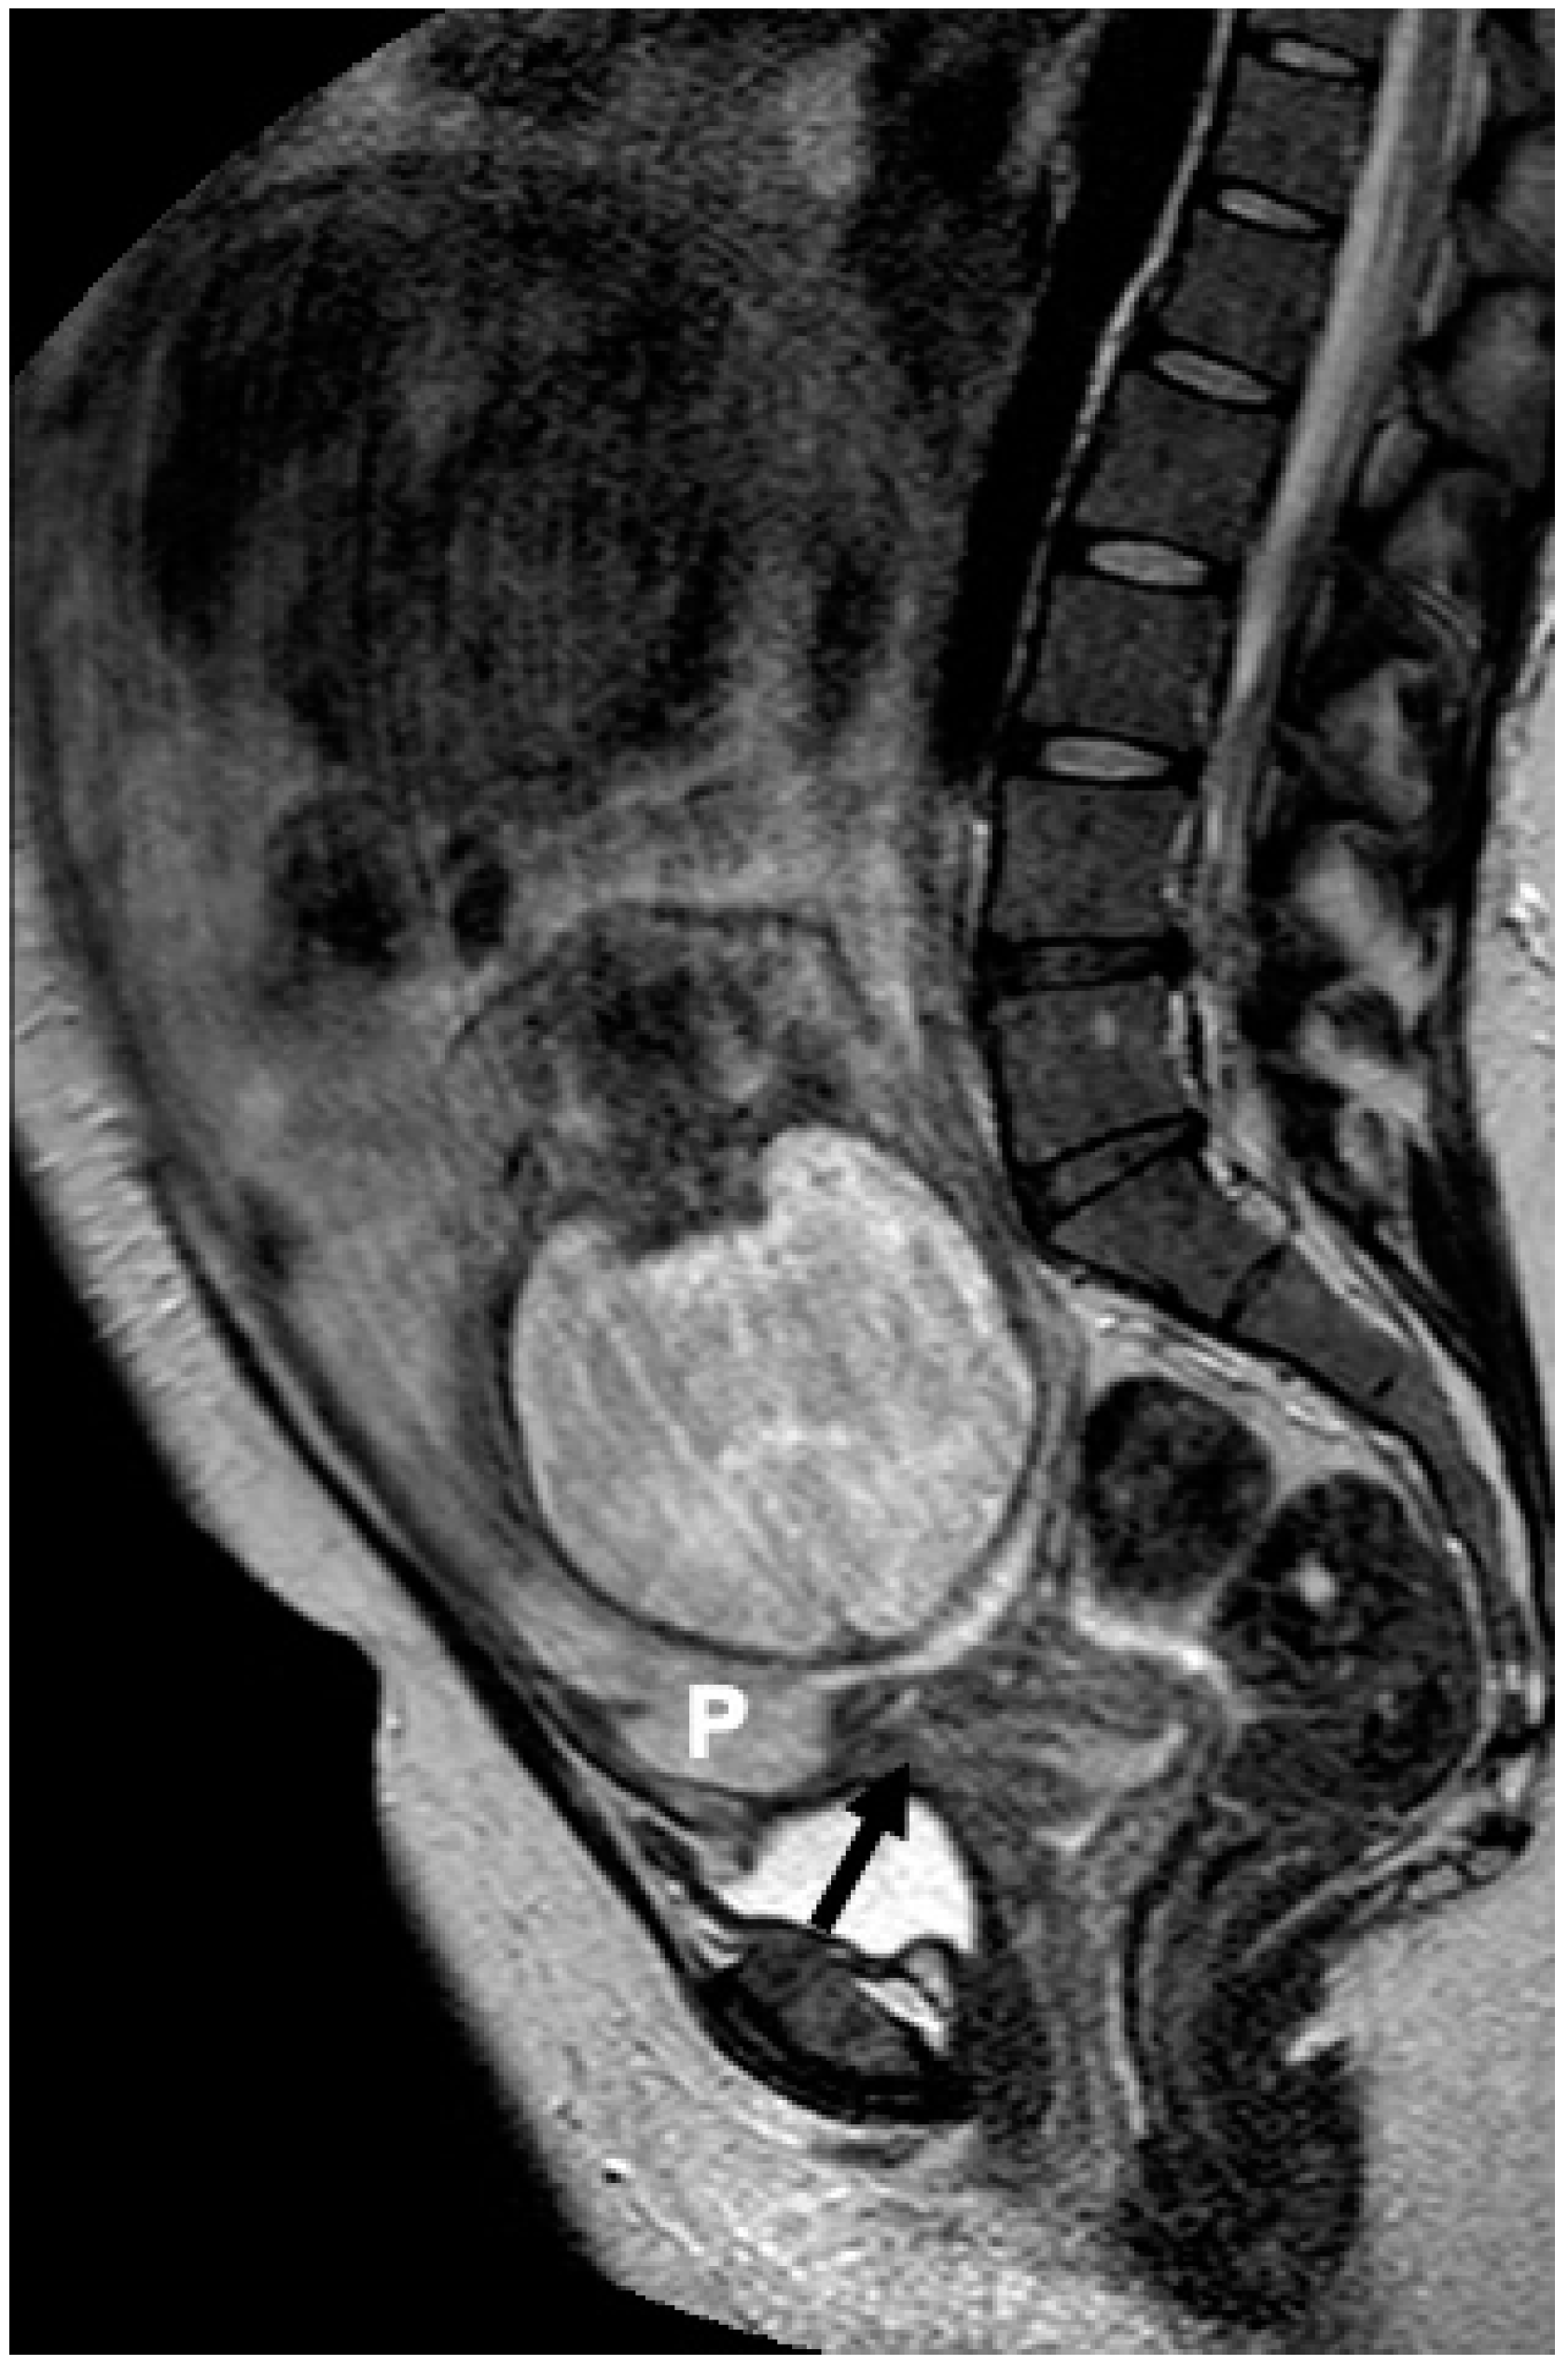

- Bourgioti, C.; Zafeiropoulou, K.; Fotopoulos, S.; Nikolaidou, M.E.; Antoniou, A.; Tzavara, C.; Moulopoulos, L.A. MRI Features Predictive of Invasive Placenta with Extrauterine Spread in High-Risk Gravid Patients: A Prospective Evaluation. Am. J. Roentgenol. 2018, 211, 701–711. [Google Scholar] [CrossRef]

- Bourgioti, C.; Zafeiropoulou, K.; Fotopoulos, S.; Nikolaidou, M.E.; Theodora, M.; Daskalakis, G.; Tzavara, C.; Chatoupis, K.; Panourgias, E.; Antoniou, A.; et al. MRI Prognosticators for Adverse Maternal and Neonatal Clinical Outcome in Patients at High Risk for Placenta Accreta Spectrum (PAS) Disorders. J. Magn. Reson. Imaging 2019, 50, 602–618. [Google Scholar] [CrossRef]

- Bourgioti, C.; Konstantinidou, A.E.; Zafeiropoulou, K.; Antoniou, A.; Fotopoulos, S.; Theodora, M.; Daskalakis, G.; Nikolaidou, M.E.; Tzavara, C.; Letsika, A.; et al. Intraplacental Fetal Vessel Diameter May Help Predict for Placental Invasiveness in Pregnant Women at High Risk for Placenta Accreta Spectrum Disorders. Radiology 2021, 298, 403–412. [Google Scholar] [CrossRef]